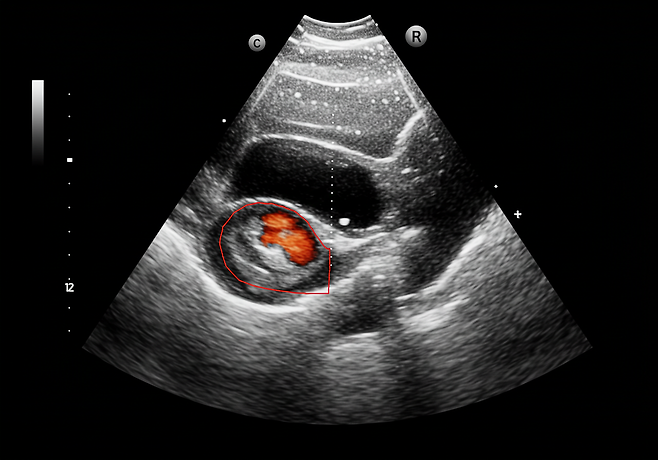

신장암은 초기 증상이 거의 없어, 암이 커져 혹이 만져지거나 혈뇨, 통증 등의 증상이 나타나면 이미 3기 이상 진행된 경우가 많습니다. 전체 환자의 약 80%는 건강검진 중 우연히 발견되며, 이때면 종양 크기가 작아 치료 성적이 좋은 편입니다.

신장암이 ‘착한 암’이라 불리는 이유도 조기 진단 시 10년 생존율이 1기에서 98%, 2기에서도 80% 이상에 이르기 때문입니다. 치료법으로는 수술적 절제가 표준이며, 신장 기능을 최대한 보존하는 부분 절제술과 로봇 수술이 선호됩니다.

정기적 건강검진과 복부 초음파 검사 병행